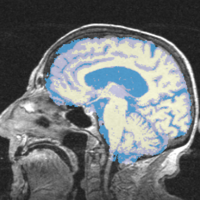

Comprehensive Longitudinal Investigation of Multiple Sclerosis at Brigham and Women’s Hospital (CLIMB) Study

- Collaborator: Svetlana Egorova MD/PhD (Brigham and Women's Hospital(BWH)), Alexander Zaitsev PhD (BWH)

- Short description: Provide Basic EM Segmentation for estimation of brain parenchymal fraction (BPF) . The processing is being performed for the cases with failing PD TDS+ segmentation. The T1-type scans are segmented and registered to PD/T2 images. The requests are being submitted over the Web GUI.

- Image specification: 1.5 Tesla ,Scanner: Varies among participants.

- Used Task: MRI Human Brain Hemisphere